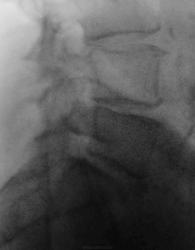

Боли в пояснице.  Пациент направлен на рентгенографию поясничного отдела позвоночника.

Очтеохондроз, 4 период.

Остеохондроз, грыжа Шморля L3. Возможно старый перелом. А, что за понятие остеохондроз 4 период. Иногда пишут стадии. Такое разграничение где-то написано?

Грыжа L3-L4

Остеохондроз, Грыжа Шморля Л2-3 диска, S-образный сколиоз

Контур и структура передней поверхности L3 в сочетании с превертебральными сосудистыми кальцинатами на этом уровне позволяют заподозрить аневризму брюшной аорты

Да, Вы правы аневризма брюшной аорты есть, она диагностирована ранее.

о тож, расслаивающая или воспалившаяся аневризма проявляет себя как раз болями в пояснице. Это уже несколько серьезнее остеохондроза